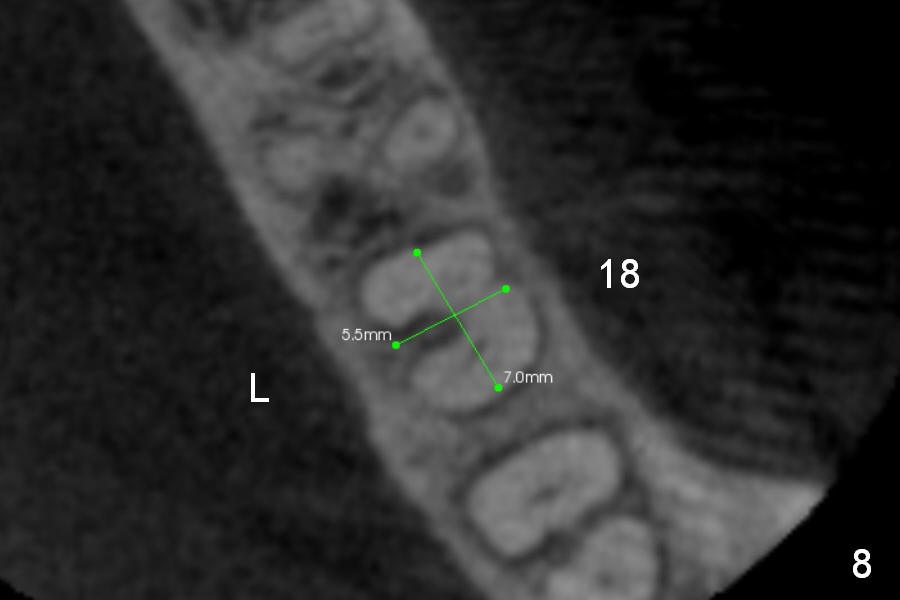

CBCT Analysis of the lower left 2nd molar reveals that the proper implant size is 5.3x10 mm (Fig.8-10). The root is C shaped; limiting factor is buccolingual width (5.5 mm, Fig.8 (axial section)). The major difference between #18 and 31 is the resorption of the buccal plate of the latter (traumatic extraction, Fig.9 (F: submandibular fossa)).